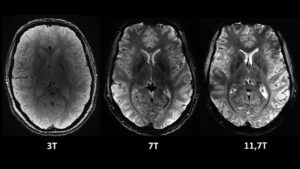

En un estreno mundial, los investigadores de la Comisión de Energía Atómica (CEA) de Francia revelaron este martes una serie de imágenes